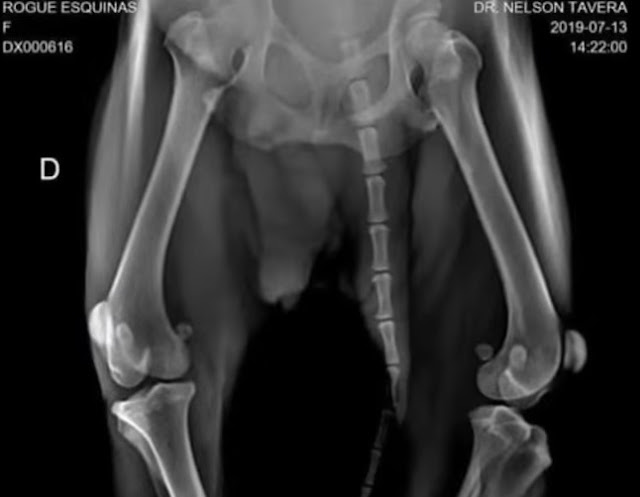

Hope’s health was in a fragile state when she was found. She has kidney issues and injuries to her back and hips, which have left her struggling to stand.

Her rear leg lacks support, and her front legs are misshapen, likely due to a calcium deficiency caused by past trauma.